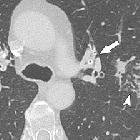

CT

May show mucosal thickening +/- calcification involving segments of the trachea and bronchi. The affected portions of the airway can also be narrowed.

When it involves the trachea, the posterior membrane is also classically involved . CT is also considered to be useful in assessing the extra-luminal extent of disease .

The distribution of the disease may be either focal or diffuse.

Occasionally the disease may manifest as a raised, tumor-like mass of amyloid material (amyloid pseudotumor / amyloidoma).